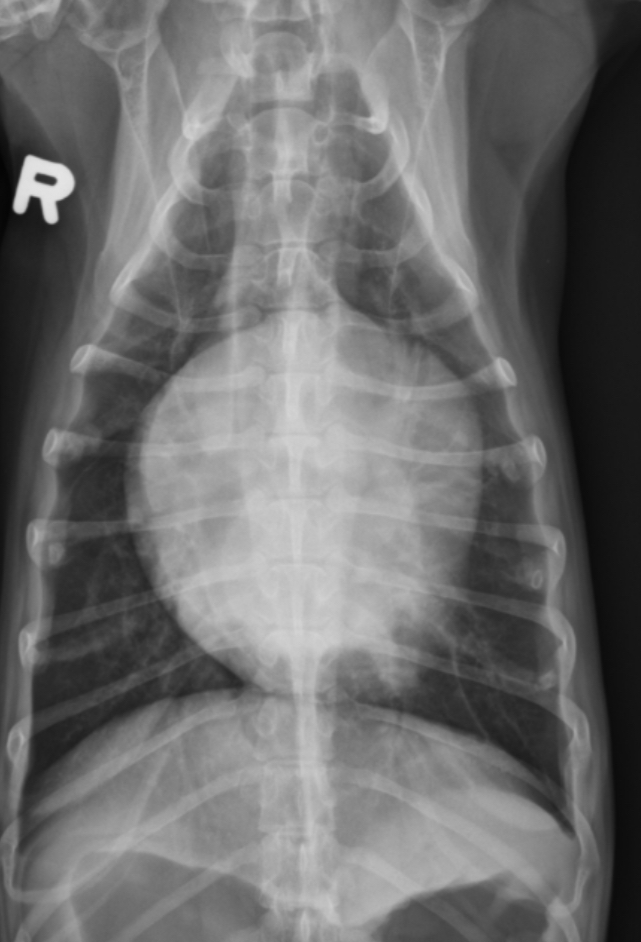

2 features of RVE on VD

-bulge 5-9 o’clock

-reverse D

What part of the heart is enlarged

RVE